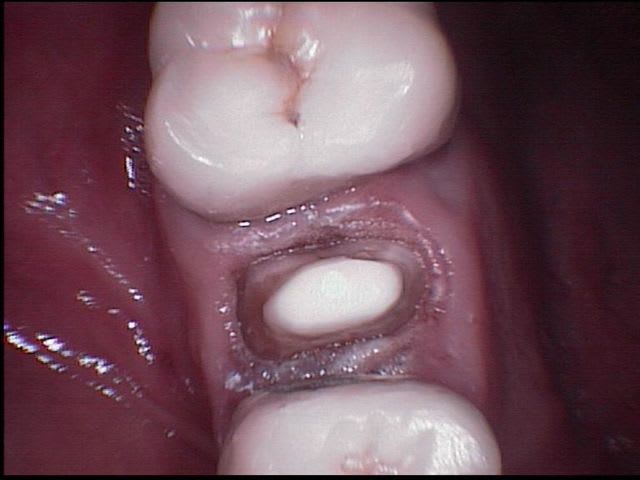

Au vu de la perte de substance, n'y avait t' il pas indication d'inlay-core?

Bof, c'est discutable (quoique perso, je préfère assurer avec un IC dans ce cas).

Mais tiens, juste pour emmerder le monde : à force d'irriguer à l'hypochlorite, qui est fortement oxydant, n'y aurait il pas un risque de voir le collage du tenon légèrement compromis ? Emma, as tu terminé ta préparation avec une irrigation à l'EDTA pour neutraliser ce fichu CloNa qui pourrait réduire l'adhésion ? (j'adore semer des doutes)

En effet Marc, irrigation EDTA pendant 5 minutes puis eau oxygénée 10 volumes + laser puis séchage au laser puis obturation, ce qui risque de compromettre le collage c'est surtout l'eugénol du sealite, mais depuis 5 à 6 ans où je fais ce type de reconstitution aucun descellement.